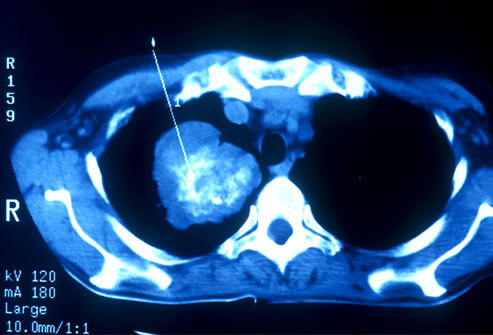

Ung thư phổi có thể được phát hiện sớm bằng chụp CT. Ở Mỹ, có một số đối tượng được khuyên đi sàng lọc ung thư phổi như những người hút thuốc hay có người thân nghiện thuốc, sống trong môi trường ô nhiễm, những người từ 55 đến 80 tuổi được khuyến cáo đi sàng lọc ung thư phổi. Nếu bệnh nhân có tiền sử hút thuốc lá nên định kỳ đi kiểm tra sức khỏe phổi. Ở những người trẻ nếu dừng hút thuốc trong vòng 15 năm có thể ngừng khám sàng lọc ung thư phổi.

Trong hầu hết các trường hợp, khi bác sĩ nghi ngờ bệnh nhân mắc ung thư phổi với các triệu chứng điển hình như ho mãn tính hoặc thở khò khè, lúc đó, bác sĩ sẽ cho người bệnh đi chụp X-quang hoặc các xét nghiệm hình ảnh khác. Bệnh nhân cũng có thể được yêu cầu xét nghiệm đờm. Nếu một trong các xét nghiệm cho thấy xuất hiện dấu hiệu của ung thư, bước tiếp theo bác sĩ sẽ tiến hành sinh thiết phổi.

Phương pháp điều trị nhắm mục tiêu là một phương thức điều trị mới của ung thư phổi, nó có thể được sử dụng cùng với hóa trị liệu hoặc khi các phương pháp điều trị khác không hiệu quả. Phương pháp nhắm mục tiêu là nhằm chặn các mạch máu tới nuôi dưỡng tế bào ung thư ở khối u. Nó có thể giúp bệnh nhân ung thư phổi sống lâu hơn. Phương pháp điều trị nhắm mục tiêu có thể làm gián đoạn các tín hiệu chịu trách nhiệm nhân lên trong tế bào ung thư trong hình ảnh ở trên.